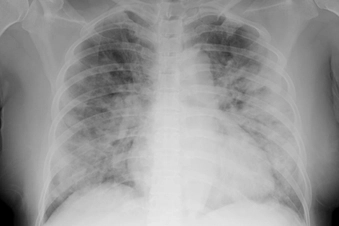

Chest Tightness or Pain

This is a telltale symptom of a more serious respiratory infection, like bronchitis. That can also make your chest feel tight, and you may have a hard time taking a deep breath. Sharp chest pain that feels worse when you cough can be a sign of pneumonia, and chest tightness is also a common symptom of asthma. Get medical help right away for any chest pain or pressure. It can also be the sign of life threatening conditions such as a heart attack or a blood clot in the lung.